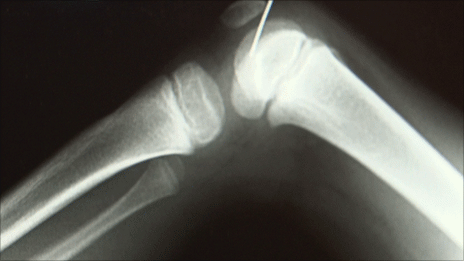

Az ilyenkor szükséges teendők elintézése (biztosító, kórházi adatfelvétel, stb.) után be is hívtak a vizsgálóba. Rögtön irány a röntgen persze. Többször is voltam már ilyen helyzetben, nem idegenkedtem a röntgentől. Elkészült a felvétel a jobb lábamról, azon belül is a térdemről.

Az orvos aggódó tekintettel jött felém, hogy miért nem szóltam, hogy valami műtétem volt korábban, és csavarok vannak a lábamban.

Elmondtam, hogy nem történt még semmilyen beavatkozás a lábamon. Újabb felvétel. Aggódó arcok. A következő pillanatban egy kulcscsomót helyeztek a lábam mellé a következő felvételhez. Közben nem mondtak semmit én pedig nem tudtam, hogy mi történik.

Az orvos közölte, hogy

egy fémdarabot találtak a lábamban. Nem értettem, hogy milyen fémről beszél, és mi az vagy hogy kerülhetett oda. Elmondták, hogy egy kis vágással ki fogják szedni.

Kiderült, egy nagy varrótű volt a "kis fémdarab".

Nem hittem a szememnek. Fogalmam sem volt, hogy hogy kerülhetett egy tű a jobb vádlimba úgy, hogy nem vettem észre és nyoma sem volt. Illetve de, mégis. Pont egy tűhegynyi pötty volt a lábamon.

A kép csak illusztráció, forrás: bbc.co.uk